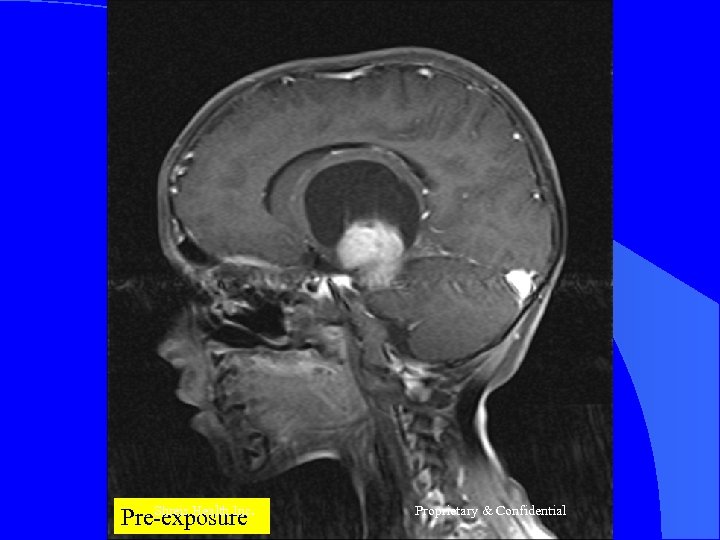

CASE 2 Mr R, 56 yrs l Nov 2004 – MRI Brain = Left frontal SOL (4 x 3 cm) - SX = Craniotomy x decompression of insular glioma HPR = Glioblastoma Grade IV l RT – 60 Gy/30 # till Jan 2005 l CT – Temedol x 2 # till Feb 2005 l Shreis Health Inc. Proprietary & Confidential

l l Presented Feb 05 - Loss of memory - Apathetic - Hemiparesis ® (power 3/5) Today after 1 course of RFQMR - No focal/Gen Neuro deficit - Normal higher functions and back to work. Shreis Health Inc. Proprietary & Confidential

Shreis Health Pre-exposure Inc. Proprietary & Confidential

Shreis Pre-exposure. Health Inc. Proprietary & Confidential